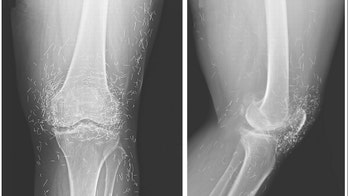

Alternative Medicine October 27, 2015 X-ray reveals hundreds of gold acupuncture needles left in woman's knees When doctors examined an X-ray image of the knees of a woman experiencing severe joint pain, they found a gold mine: hundreds of tiny gold acupuncture needles left in her tissue.